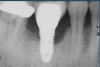

Several factors increasing the risk of peri-implantitis have been reported. Lack of access to the intaglio surface of the implant-supported prosthetics and poor oral hygiene of the implant is reported to increase the risk of peri-implantitis (Figure 3 through Figure 5). Concave intaglio design prevents oral hygiene access (Figure 6). Monje reported that 77.2% of the peri-implantitis cases had inadequate access for cleansability. 9 Serino and Ström found that 74% of the implants had no access to proper plaque control and highlighted the role of prosthesis design.10 Katafuchi suggested that a shallow emergence angle (EA) with a straight or concave transmucosal profile at the interproximal sites should be considered to minimize peri-implantitis risk for bone-level implant.11

(3.) Prosthesis without access to the intaglio interface.

Figure 3

(4.) Intagilo inflammation of the soft tissue following removal of the prosthesis.

Figure 4

(5.) Prosthesis intaglio surface.

Figure 5